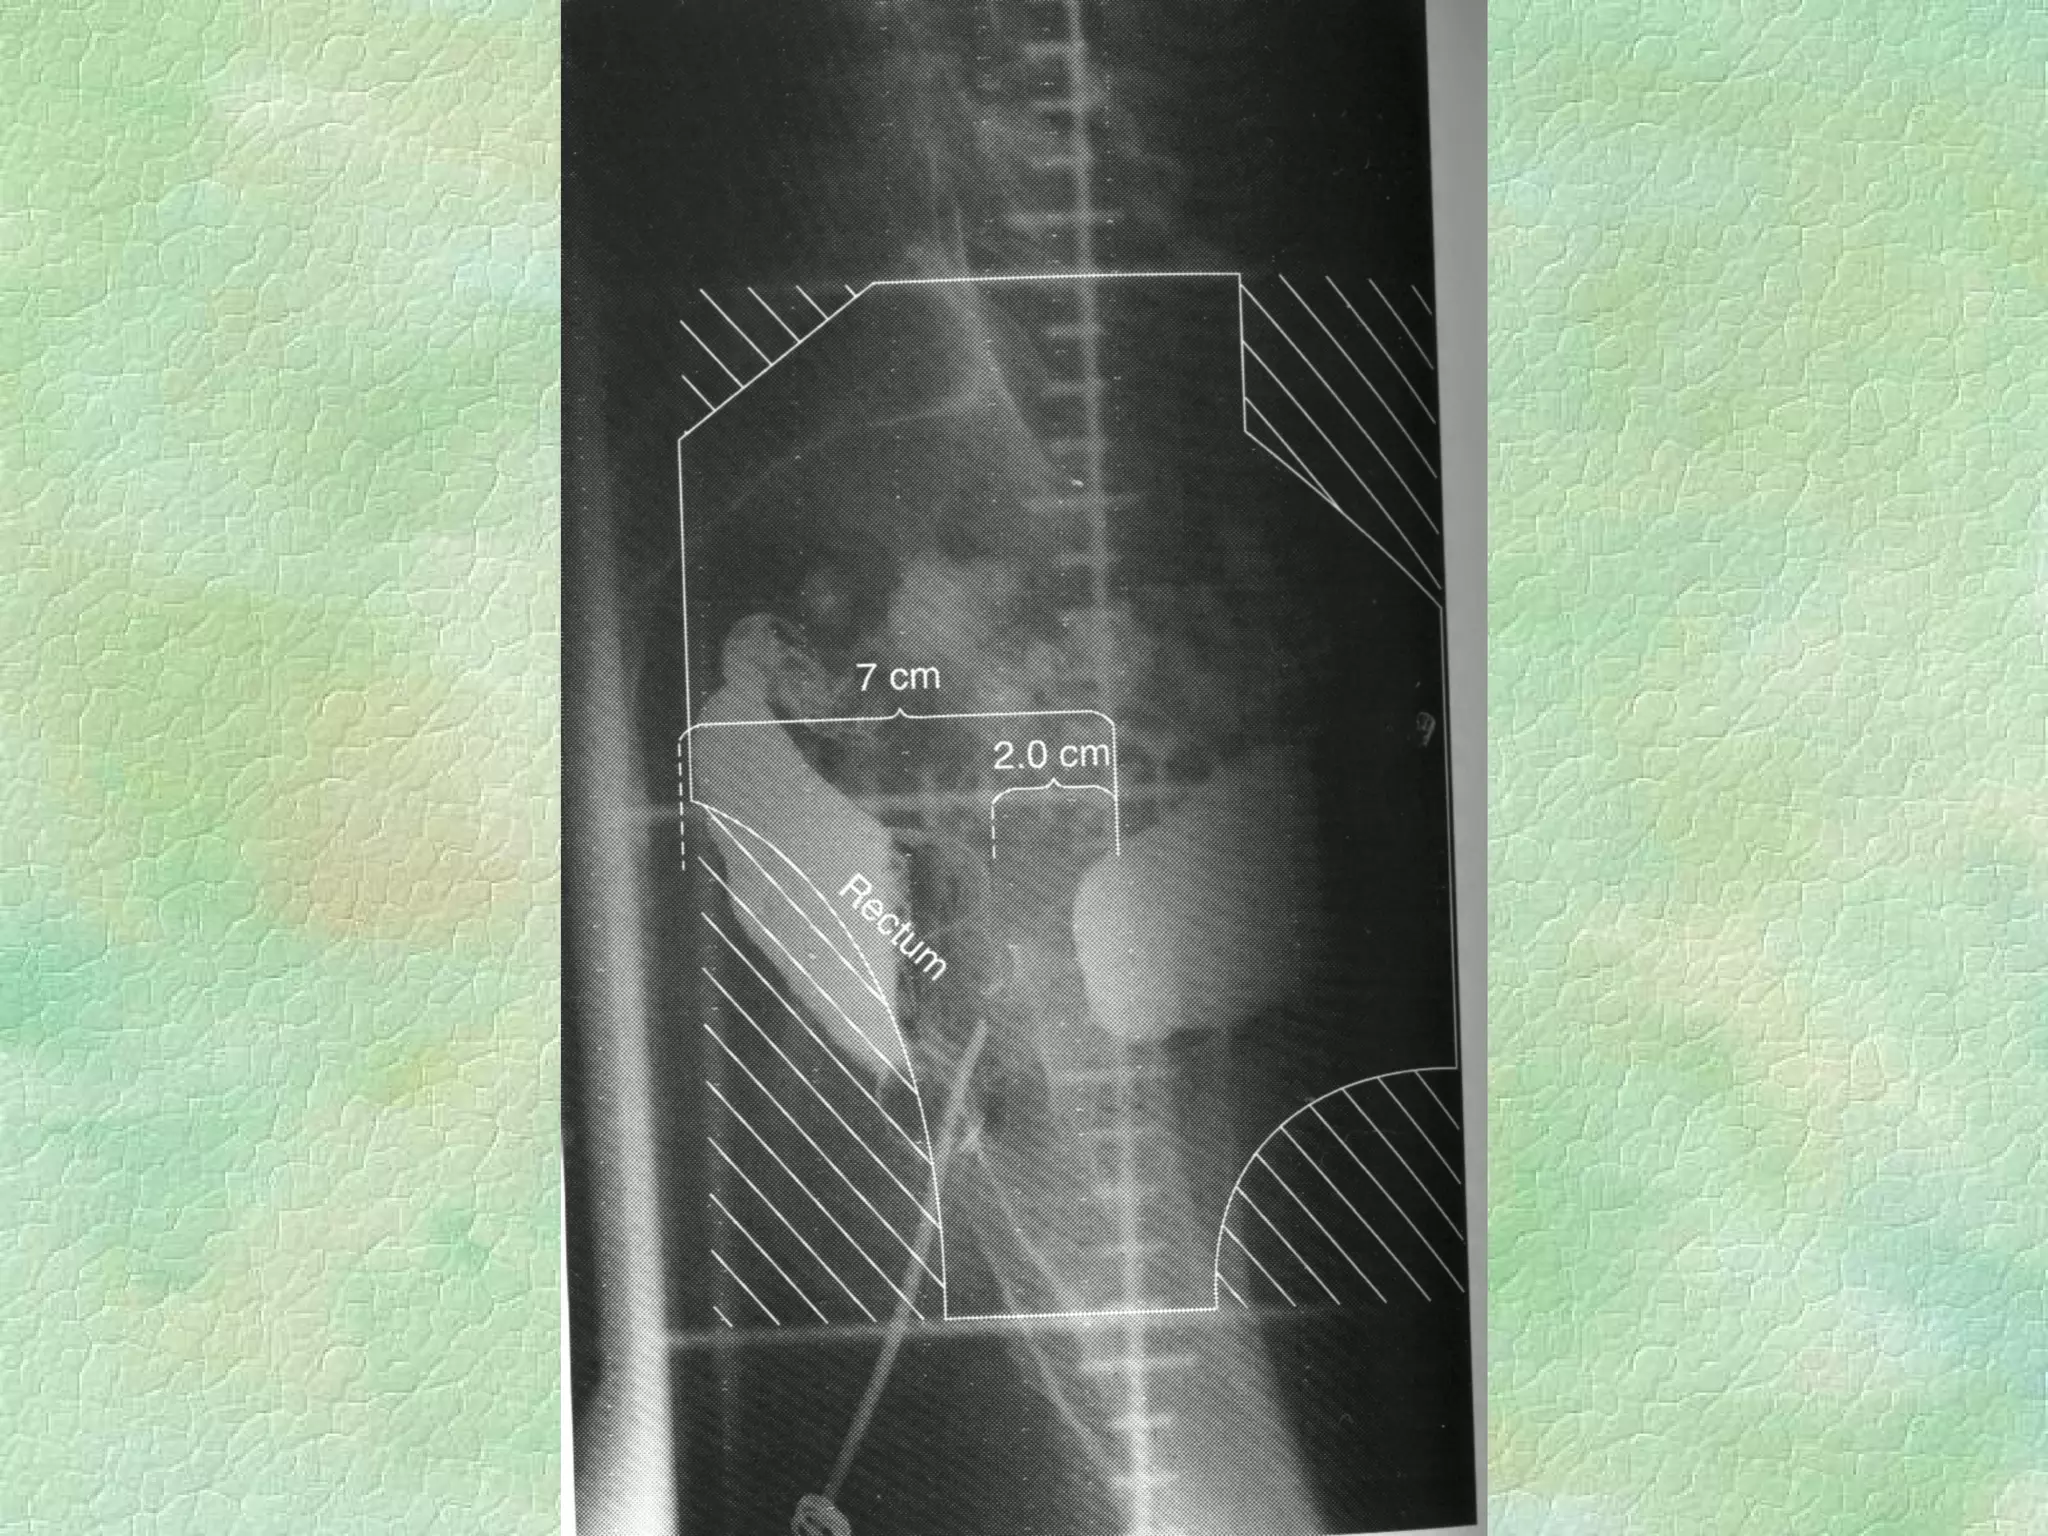

Conventional Simulation Immobilization Diagnostic energy X-rays replace Megavoltage beams Lower patient dose, better images, real-time fluoro External coordinate system same as treatment coordinate system

Volume Definition External reference palpation,visual radio-opaque markers Internal reference bony landmarks, other anatomical  transfer from CT contrast agents, internal markers

Lateral Field Nodes outlined With solder

Conventional Simulation ImmobilizationDiagnostic energy X-rays replace Megavoltage beams Lower patient dose, better images, real-time fluoro External coordinate system same as treatment coordinate system

Volume Definition Externalreference palpation,visual radio-opaque markers Internal reference bony landmarks, other anatomical transfer from CT contrast agents, internal markers

Lateral Field Nodesoutlined With solder